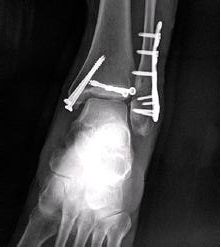

钢板固定后,防止骨折块在受到纵向力量后向外滑移。主要应用于腓骨远端。

三分之一圆周,四分之一管型已少用,非坚强固定。用于软组织膜包覆部位:外踝、鹰嘴、尺骨远端。

异形钢板之胫骨远端外侧钢板(左右式):用于胫骨远端骨折和外踝骨折(需加强应用)